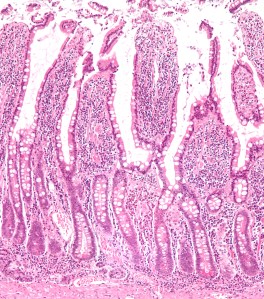

The small intestine can be a beautiful thing.